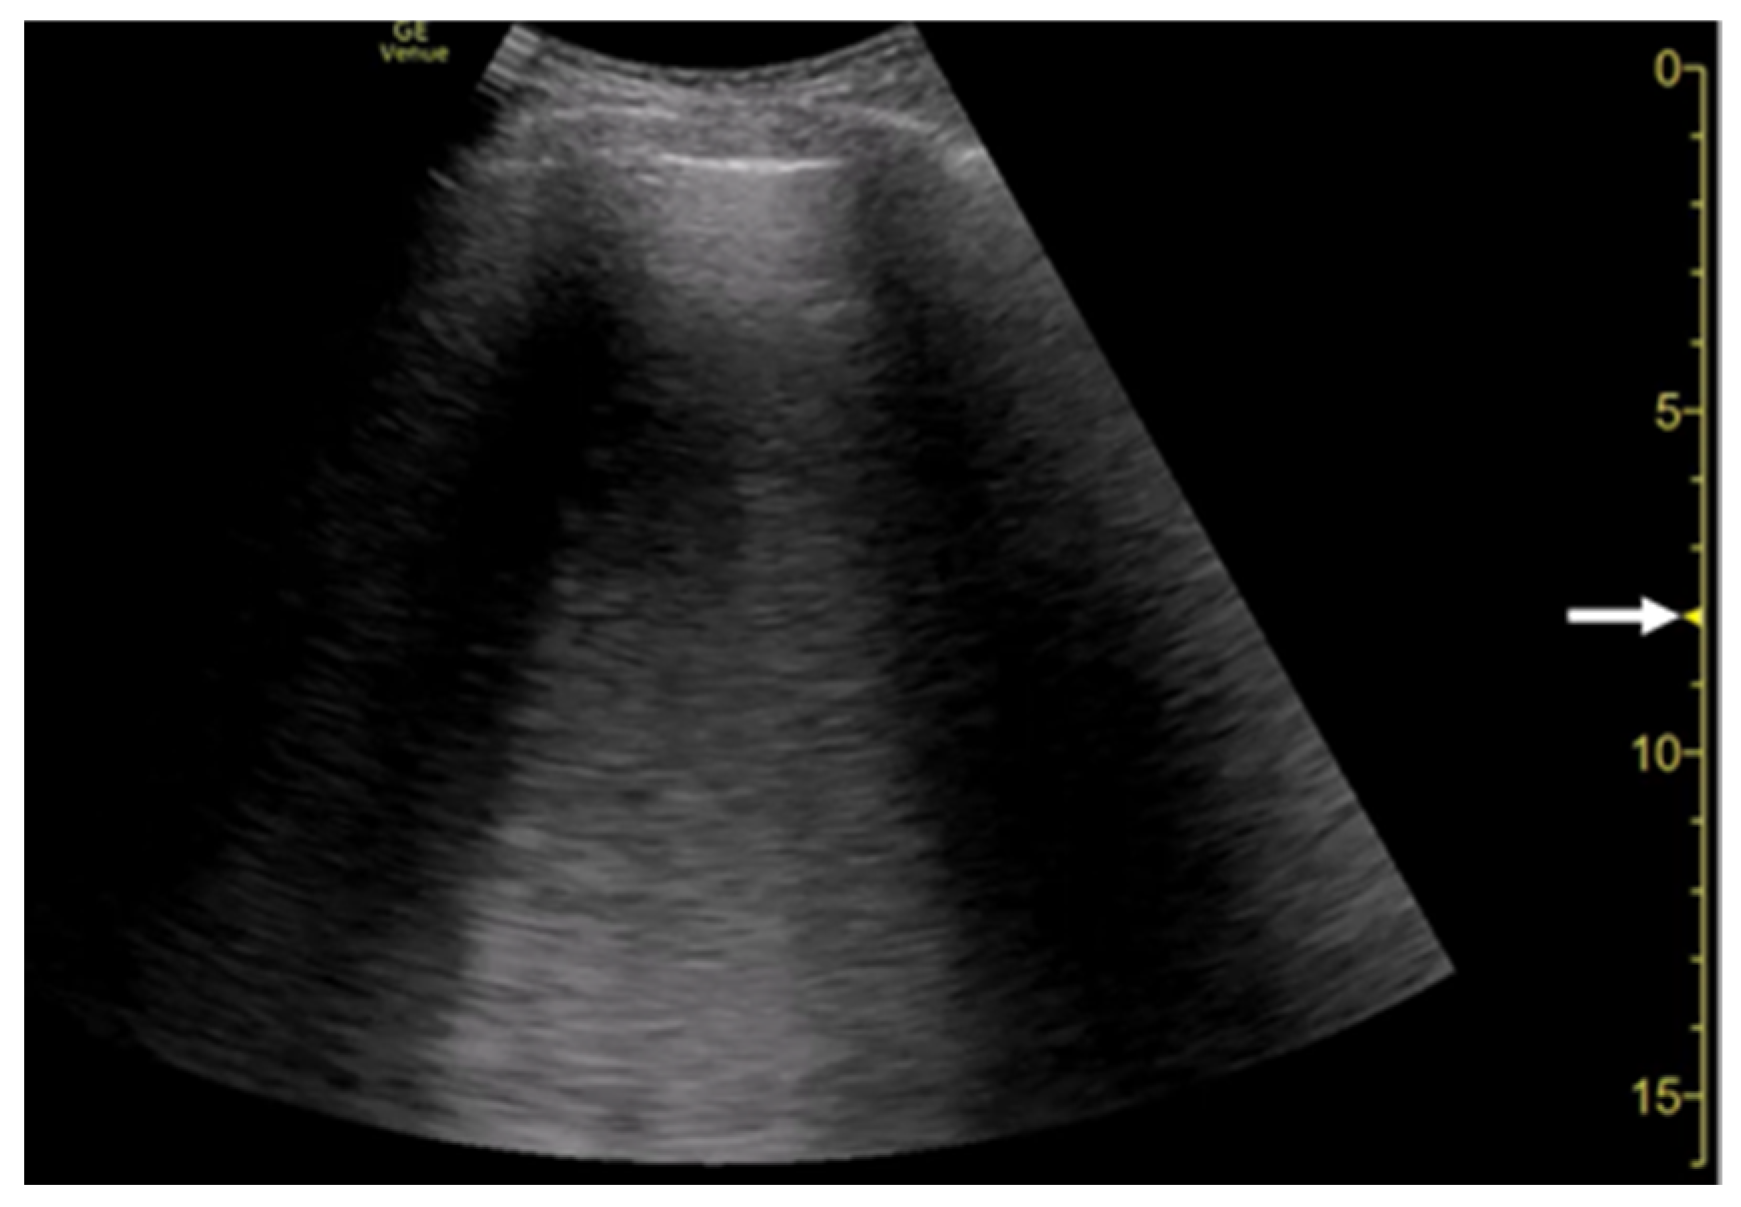

2.1. Clinical Implications

2.2. The Theory of Acoustic Trap